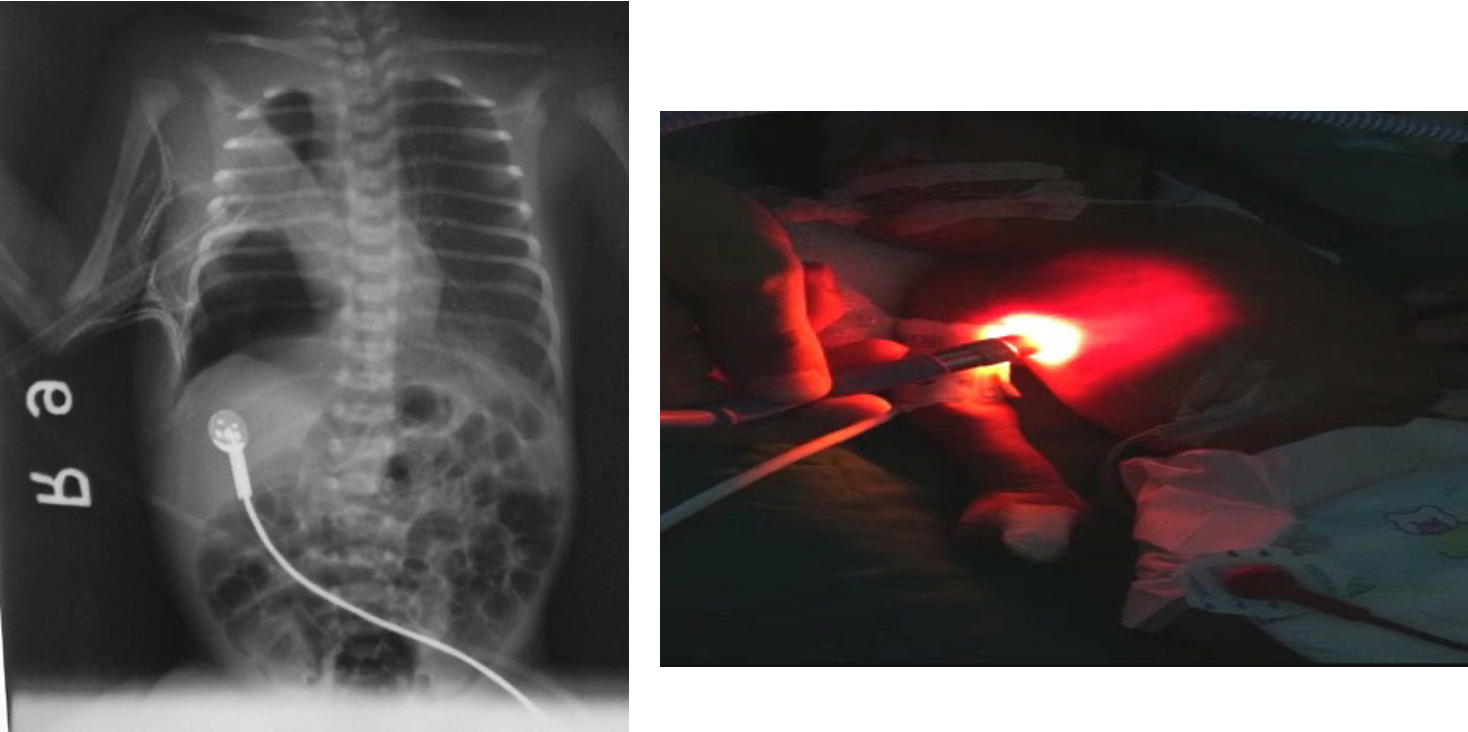

The infant has been on a ventilator for about 6 hours when you are called to the bedside for sudden decompensation with decreased saturations as low as 30%, bradycardia, and absent breath sounds on the right.

- What do you expect happened? pneumothorax

- What is your immediate action? right needle decompression 2nd intercostal mid clavical

well demarcated right lung pnumothorax - pushed

if light goes throughout lung theres pneumothoraxm if localized, its not pneumothorax.

High-intensity fiber optic light demonstrating increased transillumination on the left half of the chest suggestive of left-side pneumothorax compared to the normal right chest.